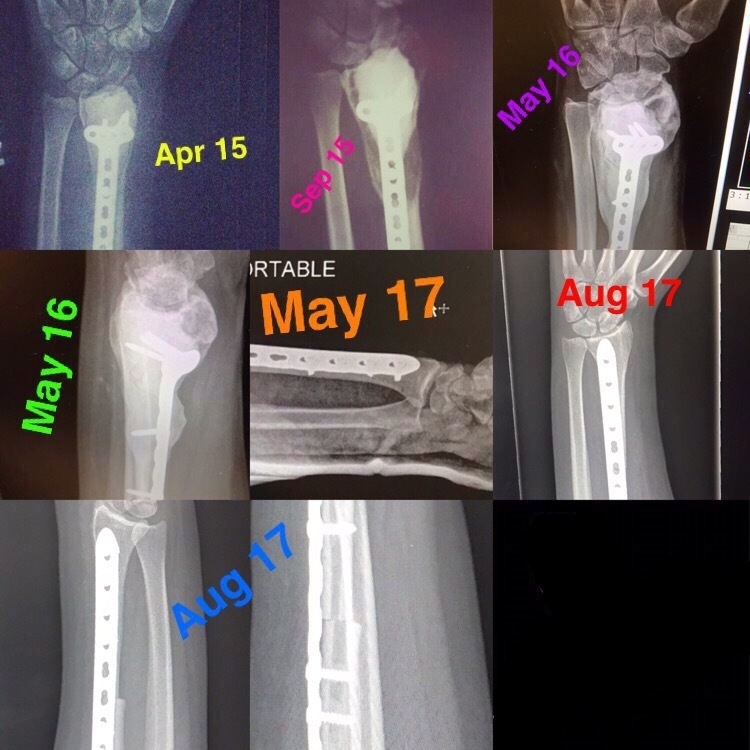

A series of x-rays detail the progression of the tumor and surgeries U.S. Air Force Staff Sgt. Jennifer Gordon, 20th Security Forces Squadron plans, programs and policy technician, underwent. Over the course of three years, Gordon went through a year of chemotherapy and three surgeries and is now in remission with no visible sign of the tumor returning. (Courtesy graphic by Senior Airman Jennifer Gordon)